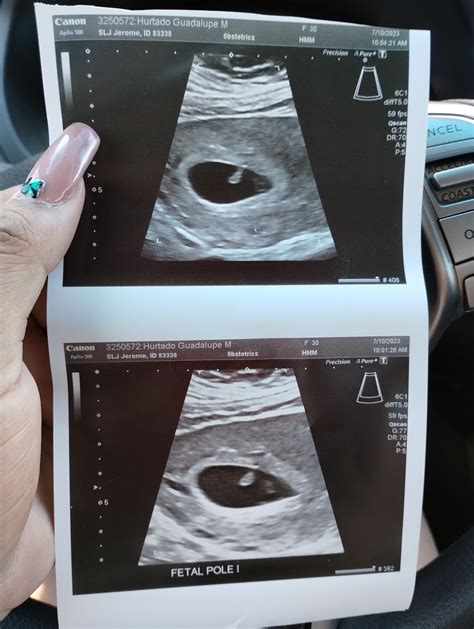

Ultrasounds at 7 weeks are typically performed to confirm the pregnancy, determine the gestational age, and check for any early signs of complications. During this stage, the embryo is still very small, measuring about 10,000 times smaller than a newborn baby. The ultrasound can help detect the presence of a gestational sac, yolk sac, and fetal pole, which are crucial indicators of a healthy pregnancy.

What Can Be Seen During an Ultrasound at 7 Weeks

At 7 weeks, the ultrasound can reveal several important structures and developments:

• Gestational Sac: This is the earliest structure that can be seen on an ultrasound, appearing as a small, fluid-filled sac within the uterus.

• Yolk Sac: This sac provides early nutrition to the embryo and is a crucial indicator of a healthy pregnancy.

• Fetal Pole: This is the earliest visible sign of the embryo itself. It appears as a small, curved structure within the gestational sac.

• Heartbeat: In some cases, a fetal heartbeat may be detected at this stage, although it is more commonly seen at 8 weeks.

These structures are essential for confirming the viability of the pregnancy and ensuring that the embryo is developing normally.